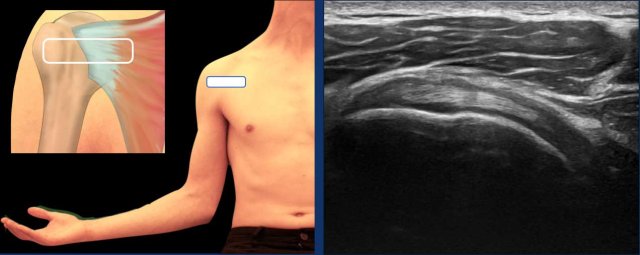

Supraspinatus tendon

The optimal position for examining the supraspinatus tendon is the modified Crass position. In this position, the patient is instructed to place their hand on the ipsilateral hip or toward their back pocket (see figure).

An alternative is the Crass position, in which the patient places their arm in internal rotation behind the back.